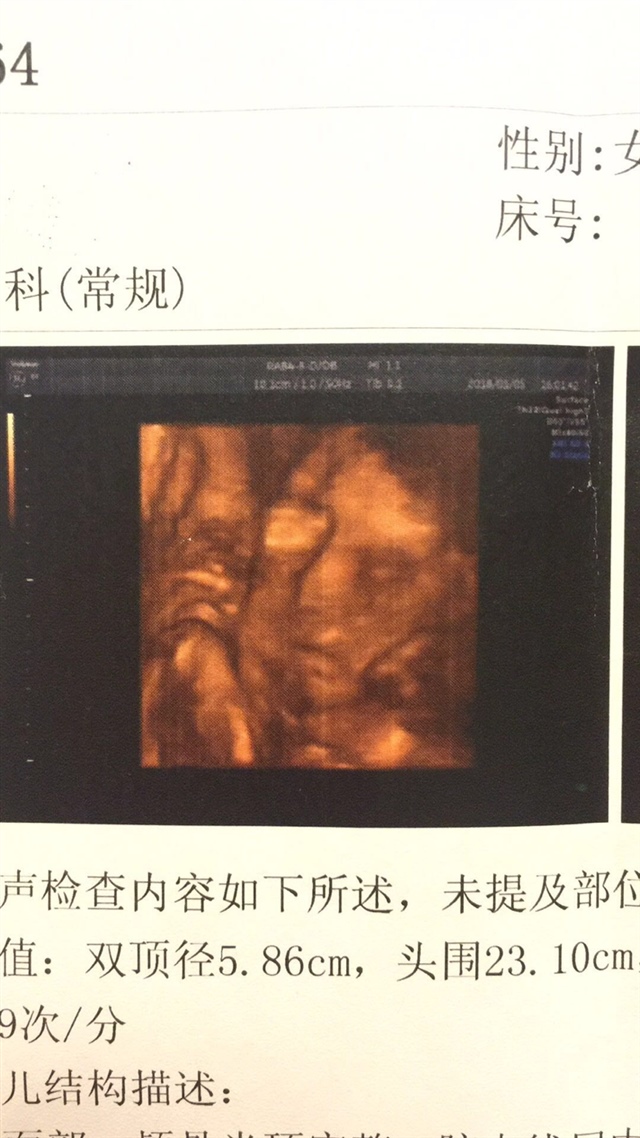

有能看数据看出来男孩女孩吗?

孕23周+1天